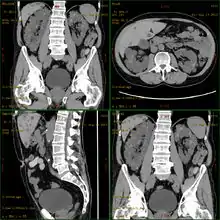

مرض الكلى المتعدد الكيسات[1] أو داء الكلى المتعددة الكيسات[1] أو تكيس الكلى[1] (بالإنجليزية: Polycystic kidney disease) ويُدعى اختصاراً PKD أو PCKD، هوَ مرض وراثي تنمو فيه كيسة غير طبيعية كبيرة في الكلية،[2] ويظهر الاضطراب الكيسي في أي مرحلة من مراحل الرضاعة والطفولة أو في مرحلة البلوغ. [3] يصيب هذا المرض الإنسان وبعض الحيوانات الأخرى. بالإضافة إلى أنه يتصف بوجود تكيسات متعددة فإنهُ عادةً ما يصيب كلا الكليتين؛ وبالرغم من ذلك فإنَّ حوالي 17٪ من الحالات المرضية في البداية يمكن ملاحظتها في كلية واحدة، وفي أغلب الحالات يتطور المرض إلى مرض ثنائي في مرحلة البلوغ.[4] يُعتبر مرض تكيس الكلى من أكثر الأمراض الوراثية شيوعًا في الولايات المتحدة حيثُ يُصيب أكثر من 60 ألف شخص، ويُصيب هذا المرض الرجال والنساء على حدٍ سواء.

![]() مرض الكلى المتعدد الكيسات | |